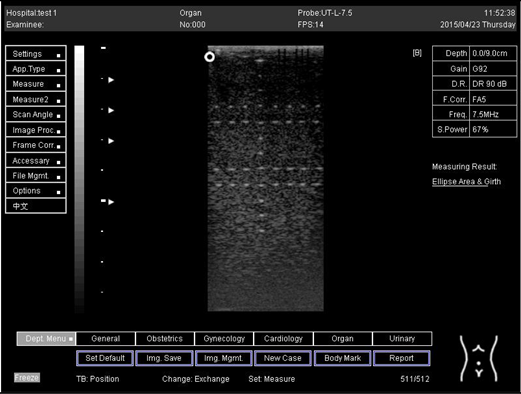

Table A6. The image taken for focal zone determination in different depth for linear probe.

Depth (cm)Diagram

5.0 The horizontal distance cannot be measured for the image of this depth

6.0 The horizontal distance cannot be measured for the image of this depth

7.0 Biomimetics 07 00130 i035

9.0 Biomimetics 07 00130 i036